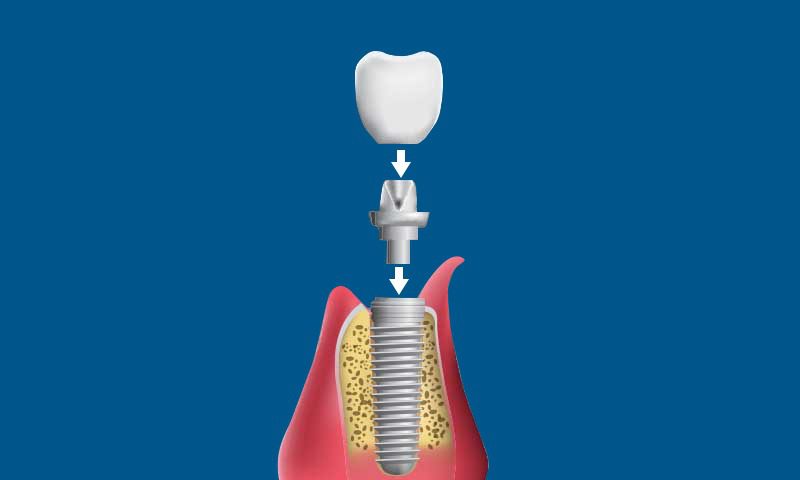

They include three pieces:

- A titanium screw placed in the jawbone

- A connector between the implant and crown

- A crown, which is the visible part of the tooth

Final Restoration. Once the healing is complete, we place a connector (abutment) on the implant and place the final crown. The completed restoration looks and functions in the same way as your natural tooth.